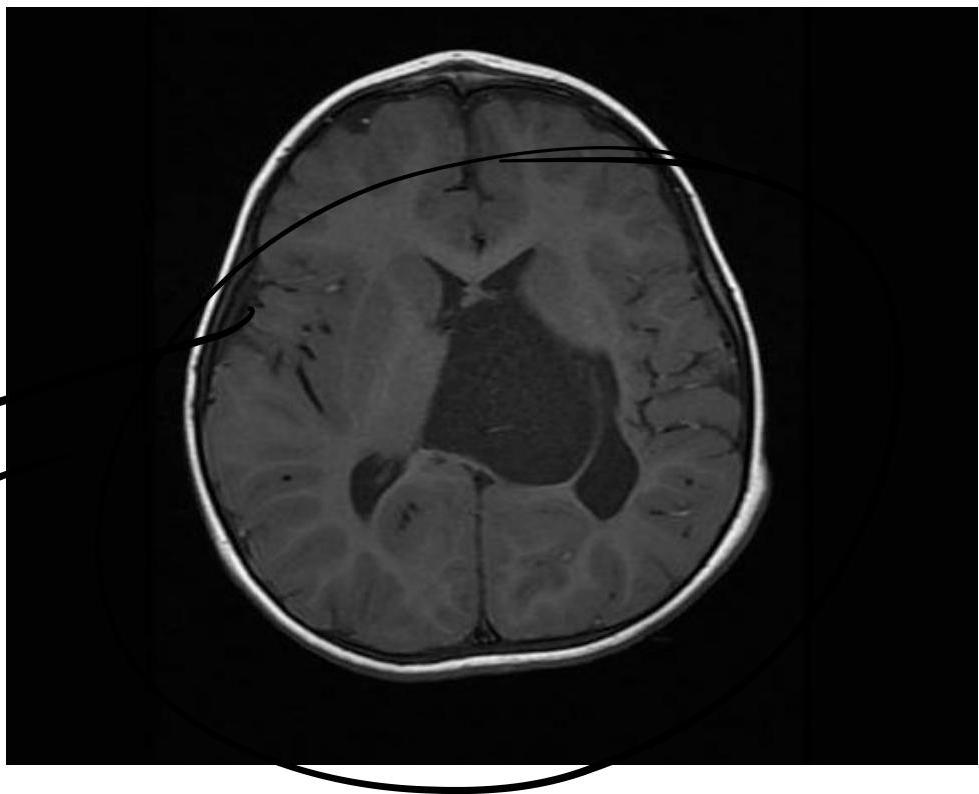

MRI Findings in Hypotonia

Modality: MRI

Findings:

- Absent corpus callosum

- Asymmetrical ventricles

- Brain atrophy

- Brain central edema

Type of Hypotonia:

- Central hypotonia